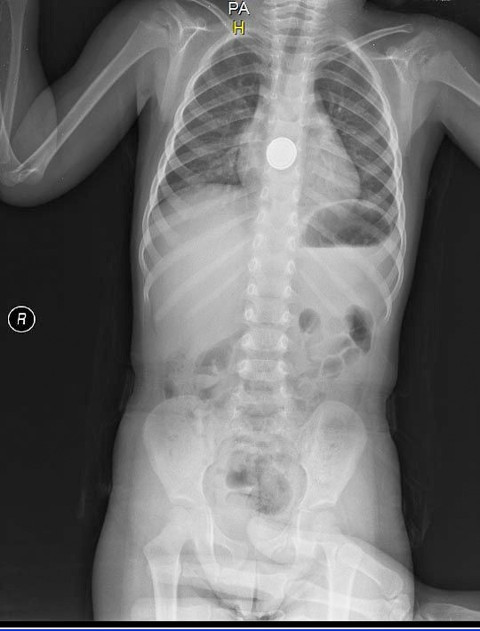

Galerinin tamamı için tıklayınızKüçük çocuk, ağzına aldığı pili yuttuktan kısa süre sonra yemek borusunda yanma hissetti. Annesinin yanına giden çocuk, 'Ben pil yuttum. Boğazım yanıyor' demesi üzerine ailesi tarafından hemen Medical Park Hastanesi Acil Servis'e götürüldü.